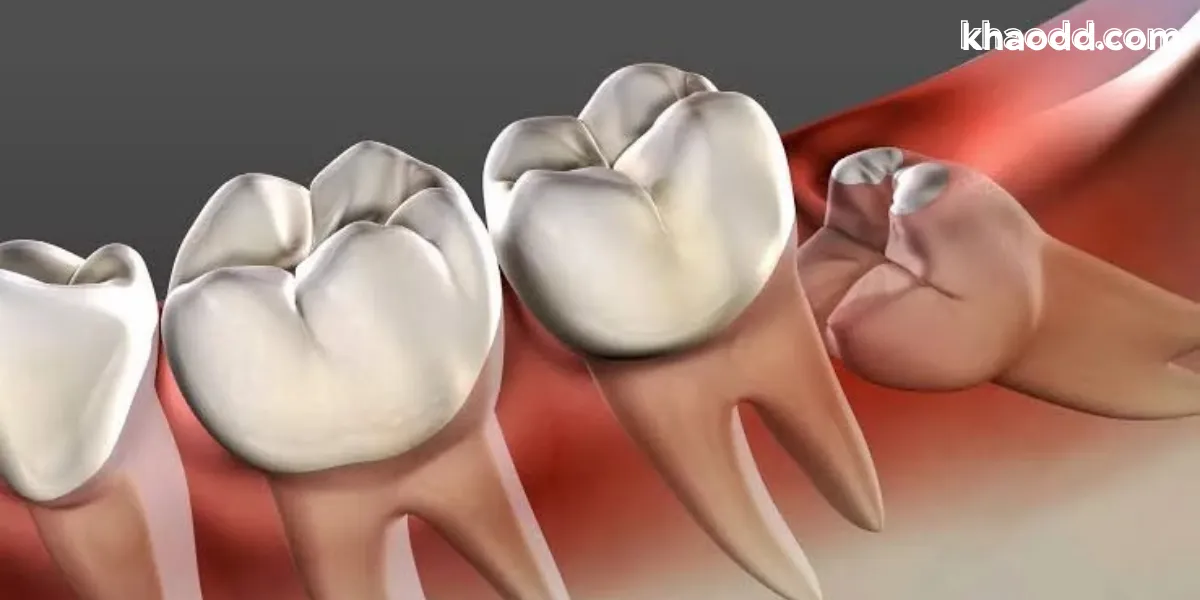

ฟันคุด คือฟันกรามซี่สุดท้ายที่มักขึ้นในช่วงวัยรุ่นถึงวัยผู้ใหญ่ตอนต้น แต่ด้วยพื้นที่ในขากรรไกรจำกัด ทำให้ฟันกรามซี่สุดท้ายไม่สามารถขึ้นได้ตามปกติ กลายเป็น “ฟันคุด” ที่ฝังตัวอยู่ใต้เหงือก หรือขึ้นเอียง ชนฟันข้างเคียง หรือโผล่ขึ้นเพียงบางส่วน ส่งผลให้เกิดการอักเสบ เจ็บปวด บวม และกลิ่นปากได้ง่าย

ปัญหาสำคัญของฟันคุดคือ ขึ้นผิดตำแหน่ง เช่น

• เอียงไปดันฟันกรามซี่ข้าง

• ขึ้นไม่เต็ม เหงือกคลุม ทำให้เศษอาหารติด

• ฝังตัวลึกในกระดูก ทำให้เกิดถุงน้ำ

• เกิดการอุดตันของช่องปากบางซี่ ทำให้แปรงฟันและทำความสะอาดได้ยากมาก

ฟันคุดที่ปล่อยไว้โดยไม่จัดการ อาจทำให้เกิดผลเสียในระยะยาว เช่น ฟันผุ เหงือกอักเสบ ฟันซ้อน ฟันเอียง หรือแม้แต่การทำลายกระดูกขากรรไกร ดังนั้นการผ่าฟันคุดจึงเป็นขั้นตอนที่ทันตแพทย์แนะนำเพื่อป้องกันปัญหาเหล่านี้ตั้งแต่เนิ่น ๆ